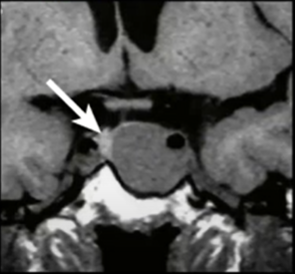

IRM des pathologies hypophysaires